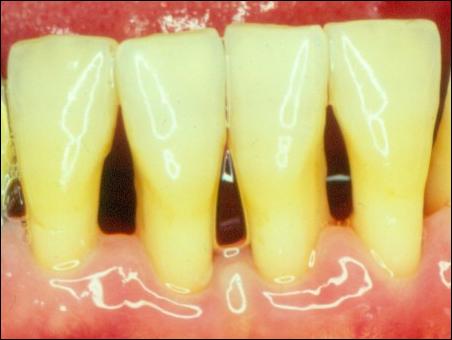

掛滿了結(jié)石的牙齦組織紅腫

潔完牙后,牙齦組織恢復成粉白色,不再充血發(fā)炎